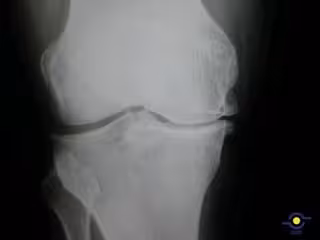

La artrosis es la enfermedad articular más frecuente, lesiona el cartílago articular, y generalmente presenta una evolución lenta y progresiva. En concreto, provoca una reducción del movimiento de la articulación y dolor, principalmente cuando se realiza alguna actividad física y suele disminuir la sintomatología con el reposo en el caso de la artrosis de rodilla o cadera.

El portavoz de la SER, el doctor Jordi Monfort, informa que la más relevante es la prevalencia en artrosis de rodilla que afecta al 10,2% de la población, le siguen la de manos y cadera que rondan el 6% de afectados.